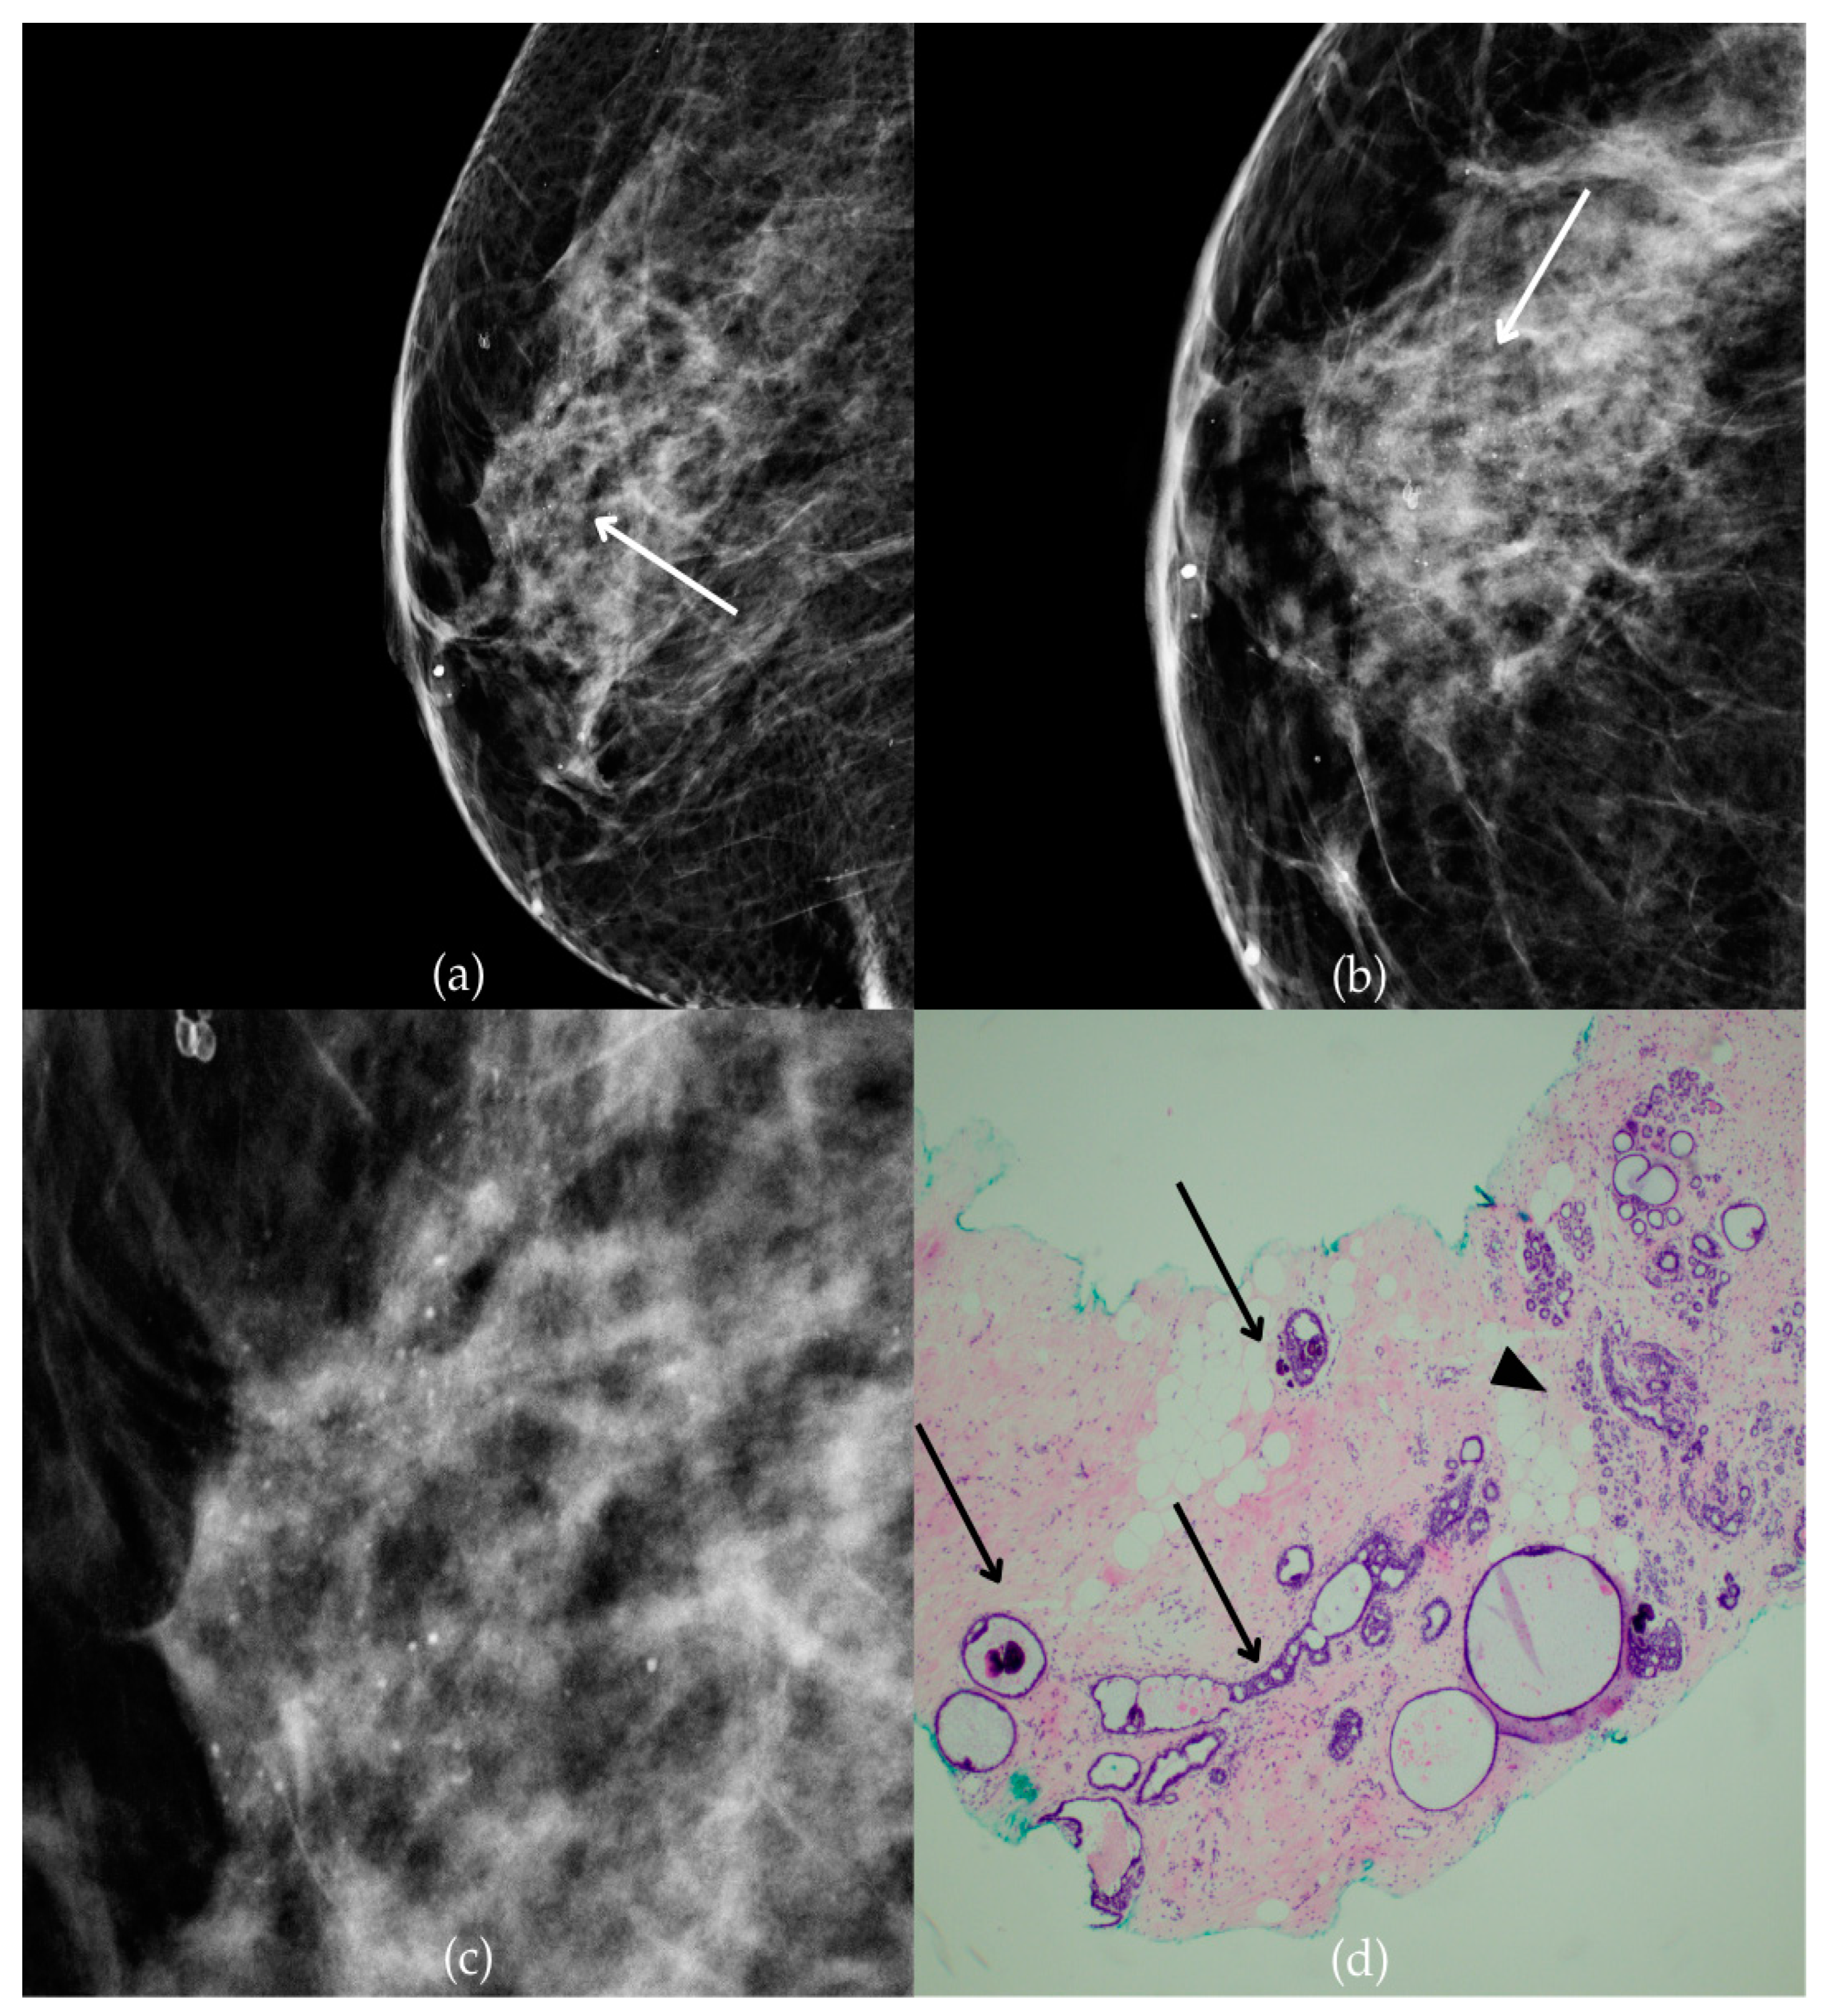

The mammogram and histopathological images (Figure 4) of the 62-year-old patient’s left breast show grouped coarse heterogeneous calcifications in the upper outer quadrant, corresponding to a BI-RADS 3 finding. Tissue analysis obtained through biopsy indicated the presence of an invasive carcinoma (category B5b). The patient underwent quadrantectomy, and postoperative pathology confirmed the diagnosis of invasive carcinoma. The patient’s most recent MRI, performed two years after the initial diagnosis, was assessed as BI-RADS 2, suggesting benign changes.

Figure 4.

Invasive breast cancer. (a) Mediolateral oblique (MLO) mammography view; (b) craniocaudal (CC) mammography view of the left breast showing grouped coarse heterogeneous calcifications (marked with arrows) in the upper outer quadrant. (c) Magnified mammographic image of grouped coarse heterogeneous calcifications. (d) The histopathological image of the biopsy sample shows the characteristic features of invasive cancer (marked with arrow) and ductal carcinoma in situ (DCIS) (marked with arrowhead) (HE staining; 40× magnification).